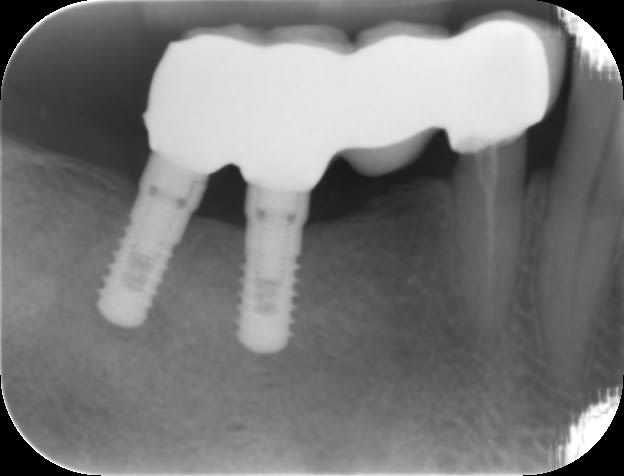

Un patient que je suis régulièrement s'est présenté avec un bridge implanto-dento porté descellé. Les piliers sont dévissés. Les vis sont solidaires des piliers.

Quelqu'un peut-il me dire si il connaît la marque et comment faire pour revisser ce type de pilier car il n'y a pas de puits de vis. Existe-t-il un instrument spécifique ?

ONB de chez IDI...

les piliers utilisés sont des piliers pleins qui ont été préparés en bouche à la turbine...